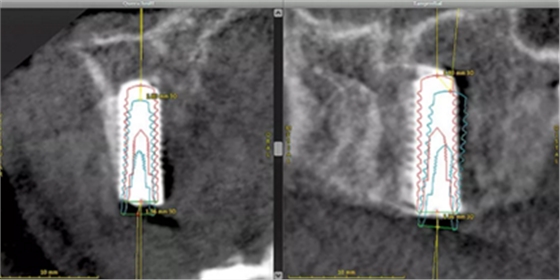

據(jù)有關(guān)文獻(xiàn),在使用CBCT輔助制作種植體導(dǎo)板時,種植體位置偏差為0.43mm,角度偏差4度。粘膜支持式導(dǎo)板誤差為0.7-0.9mm之間,牙支持式外科導(dǎo)板往往表現(xiàn)出更高的精確度。但在該手術(shù)中,平均角度誤差為1.78度,種植體體部和種植體頂端的3D偏置平均值分別為0.63mm和0.89mm,指數(shù)誤差均在所需的范圍內(nèi)。以上數(shù)據(jù)經(jīng)治療評估工具 (coDiagnostixTM) 檢查得出(圖 12)。

(圖12)